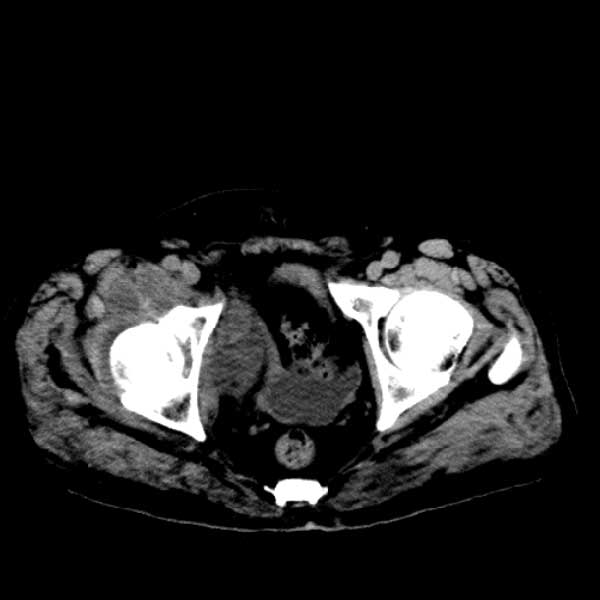

标题: CT13513:男 71 腹部疼痛20余天,近几天高热就诊,骨窗未见异 [打印本页]

标题: CT13513:男 71 腹部疼痛20余天,近几天高热就诊,骨窗未见异

考虑感染性病变可能性大,起源于阑尾?

感染,脓肿形成

考虑为化脓性阑尾炎.脓肿形成.及多肌肉累及.

考虑右侧腰大肌脓肿,向右髂窝、右腹股沟流注。

支持化脓性阑尾炎伴右髂窝脓肿、腰大肌腰方肌脓肿形成。

考虑腹腔及盆腔化脓性炎症,累及右侧髋关节及腹股沟区.

首先考虑化脓性阑尾炎伴腰大肌、腰方肌脓肿,不除外回盲部结核。

回盲部癌待排除。

患者肠镜检查考虑结肠癌,病理证实

患者肠镜检查考虑结肠癌,病理证实。肺部ct可见多发结节,考虑转移